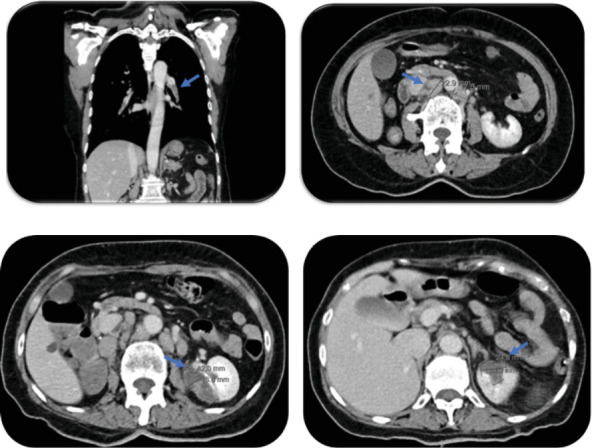

非细菌性血栓性心内膜炎是一种罕见的疾病,其特征是在心脏瓣膜上形成非感染性植物。它与系统性栓塞现象有关,主要发生在癌症晚期,特别是腺癌。这是一种基于临床背景的排除诊断,超声心动图显示的植被,阴性血培养,和感染性心内膜炎之间的区别是具有挑战性的。我们报告一个病例66岁的妇女,既往治疗乳腺和尿路上皮癌的历史,提出了体质综合征和肺血栓栓塞。计算机断层扫描显示全身栓塞现象和腹膜后淋巴结病变。在超声心动图上发现二尖瓣的植被,引起严重的二尖瓣反流,导致严重的急性心力衰竭,最终导致患者死亡。随后的淋巴结活检免疫组化结果显示尿路上皮癌复发。

Nonbacterial thrombotic endocarditis is a rare condition characterized by the formation of noninfectious vegetations on the heart valves. It is related with systemic embolic phenomena occurring predominantly in advanced cancer stages, particularly adenocarcinomas. It is a diagnosis of exclusion based on the clinical context, echocardiographic findings of a vegetation, and negative blood cultures, and distinction between infective endocarditis is challenging. We report a case of a 66-year-old woman, with history of previously treated breast and urothelial carcinoma, presenting with constitutional syndrome and pulmonary thromboembolism. Computed tomography scan revealed systemic embolic phenomena and retroperitoneal lymphadenopathies. A vegetation in the mitral valve constituted a finding on echocardiography, causing severe mitral regurgitation, which led to severe acute heart failure and culminated in patient's death. Subsequent results of immunohistochemistry of the lymph node biopsy yielded the recurrence of urothelial carcinoma.